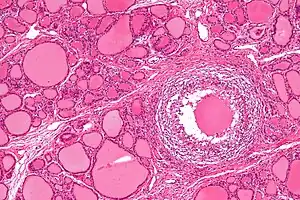

| Micrograph showing a granuloma in subacute granulomatous thyroiditis. H&E stain. | |

In subacute granulomatous thyroiditis, there is infiltration of neutrophils and other immune cells which cause damage to the thyroid follicular cells. The damage leads to formation of granulomas with multi-nucleated giant cells and associated fibrosis.[3][4][5][8] In contrast, subacute lymphocytic thyroiditis is characterized by an infiltration of lymphocytes causing damage to the thyroid gland, similar to Hashimoto's thyroiditis.[8]